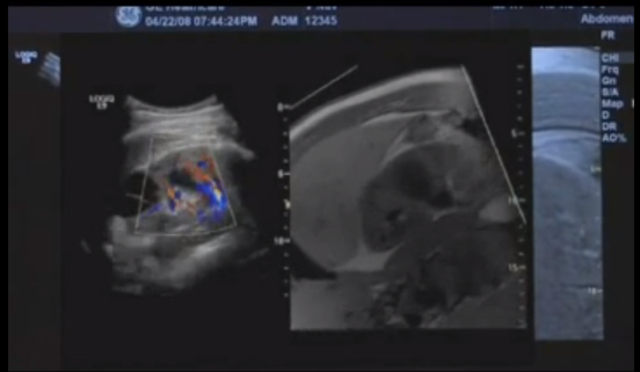

• Launch of the Logiq E9 after 5 years of research and development. A launch team was formed for clinical testing as well as to train the applications team on new features. This team would consist of 8 senior applications members and 6 engineers.

-The Logiq E9 introduced multimodality fusion a new technology to end users. -The challenge for the launch team was how to educate customers as well as the full applications team. -Need for multimodaility fusion educational materials was noted.